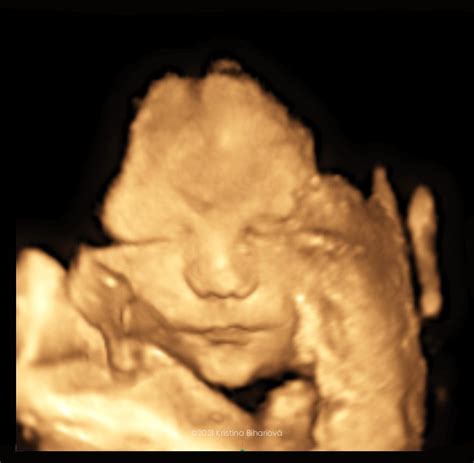

3D, 4D ultrazvuk vs. 2D ultrazvuk

Zatiaľ čo štandardné "povinné" prenatálne ultrazvuky sa robia 2D formou, 3D ultrazvuk predstavuje statické zobrazenie plodu v priestore. Trojrozmerný obraz sa dosahuje počítačovým spracovaním súboru nakumulovaných 2D obrazov. Ďalšou možnosťou je 4D zobrazenie, ktoré sa od plastického 3D obrazu líši jedným faktorom navyše - časom/pohybom. Snímku vidíte v priamom prenose, môžete sledovať, ako sa dieťa hýbe a sledovať jeho mimiku. Toto vyšetrenie je špeciálne zobrazenie bábätka, ktoré vidíte trojrozmerne. Z takéhoto vyšetrenia vám zvyčajne lekár natočí video, na ktorom vidíte aj pohyb dieťatka v reálnom čase. Môžete vidieť, aké má vaše bábätko črty, či dokonca na koho sa podobá. Samozrejme, toto vyšetrenie má svoje limity, nie vždy je úplne zreteľné a vydarené, ale medzi budúcimi mamami je pomerne obľúbené. Lekár vám môže aj vytlačiť 3D fotografiu dieťatka.

Pri rozšírenom morfologickom, genetickom ultrazvuku sa navyše sleduje profil tváre (ústa, pery, nos), jednotlivé časti mozgu, stav dôležitých ciev a ich prietoky, podrobne sa vyšetruje bránica a srdce, využíva sa 3D/4D zobrazenie.